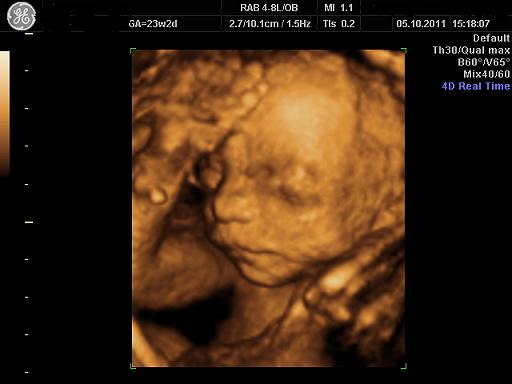

Mam do Was pytanie dziewczyny - jak jest ułożony Wasz dzidziuś?? Bo moja córcia przez 3 miesiące była główką w dół - gotowa do porodu, a wczoraj na wizycie okazało się, że się odwróciła o 180 stopni - moj gin dal jej 3 tygodnie do nastepnej wizyty zeby z powrotem sie ustawiła, jak tego nie zrobi to male szanse na porod silami natury - pozostaje cesarka, której bardzo bym nie chciala... takiego psikusa zrobiła nam nasza kruszynka... Myślicie, że mamy jeszcze szanse - to juz wlasciwie 31 tydzien...